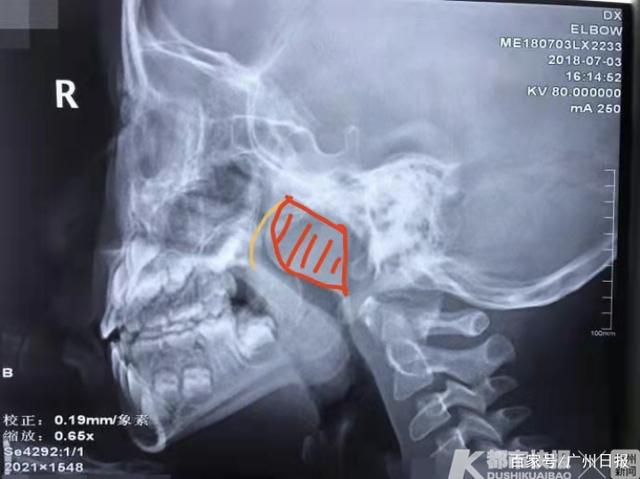

腺样体增大的x线测量与诊断

腺样体肥大的x线诊断

通过x线测量腺样体肥大的4种方法

儿童腺样体肥大 做的相关检查 鼻咽部侧位x片怎么看

儿童腺样体肥大影像表现及诊断标准